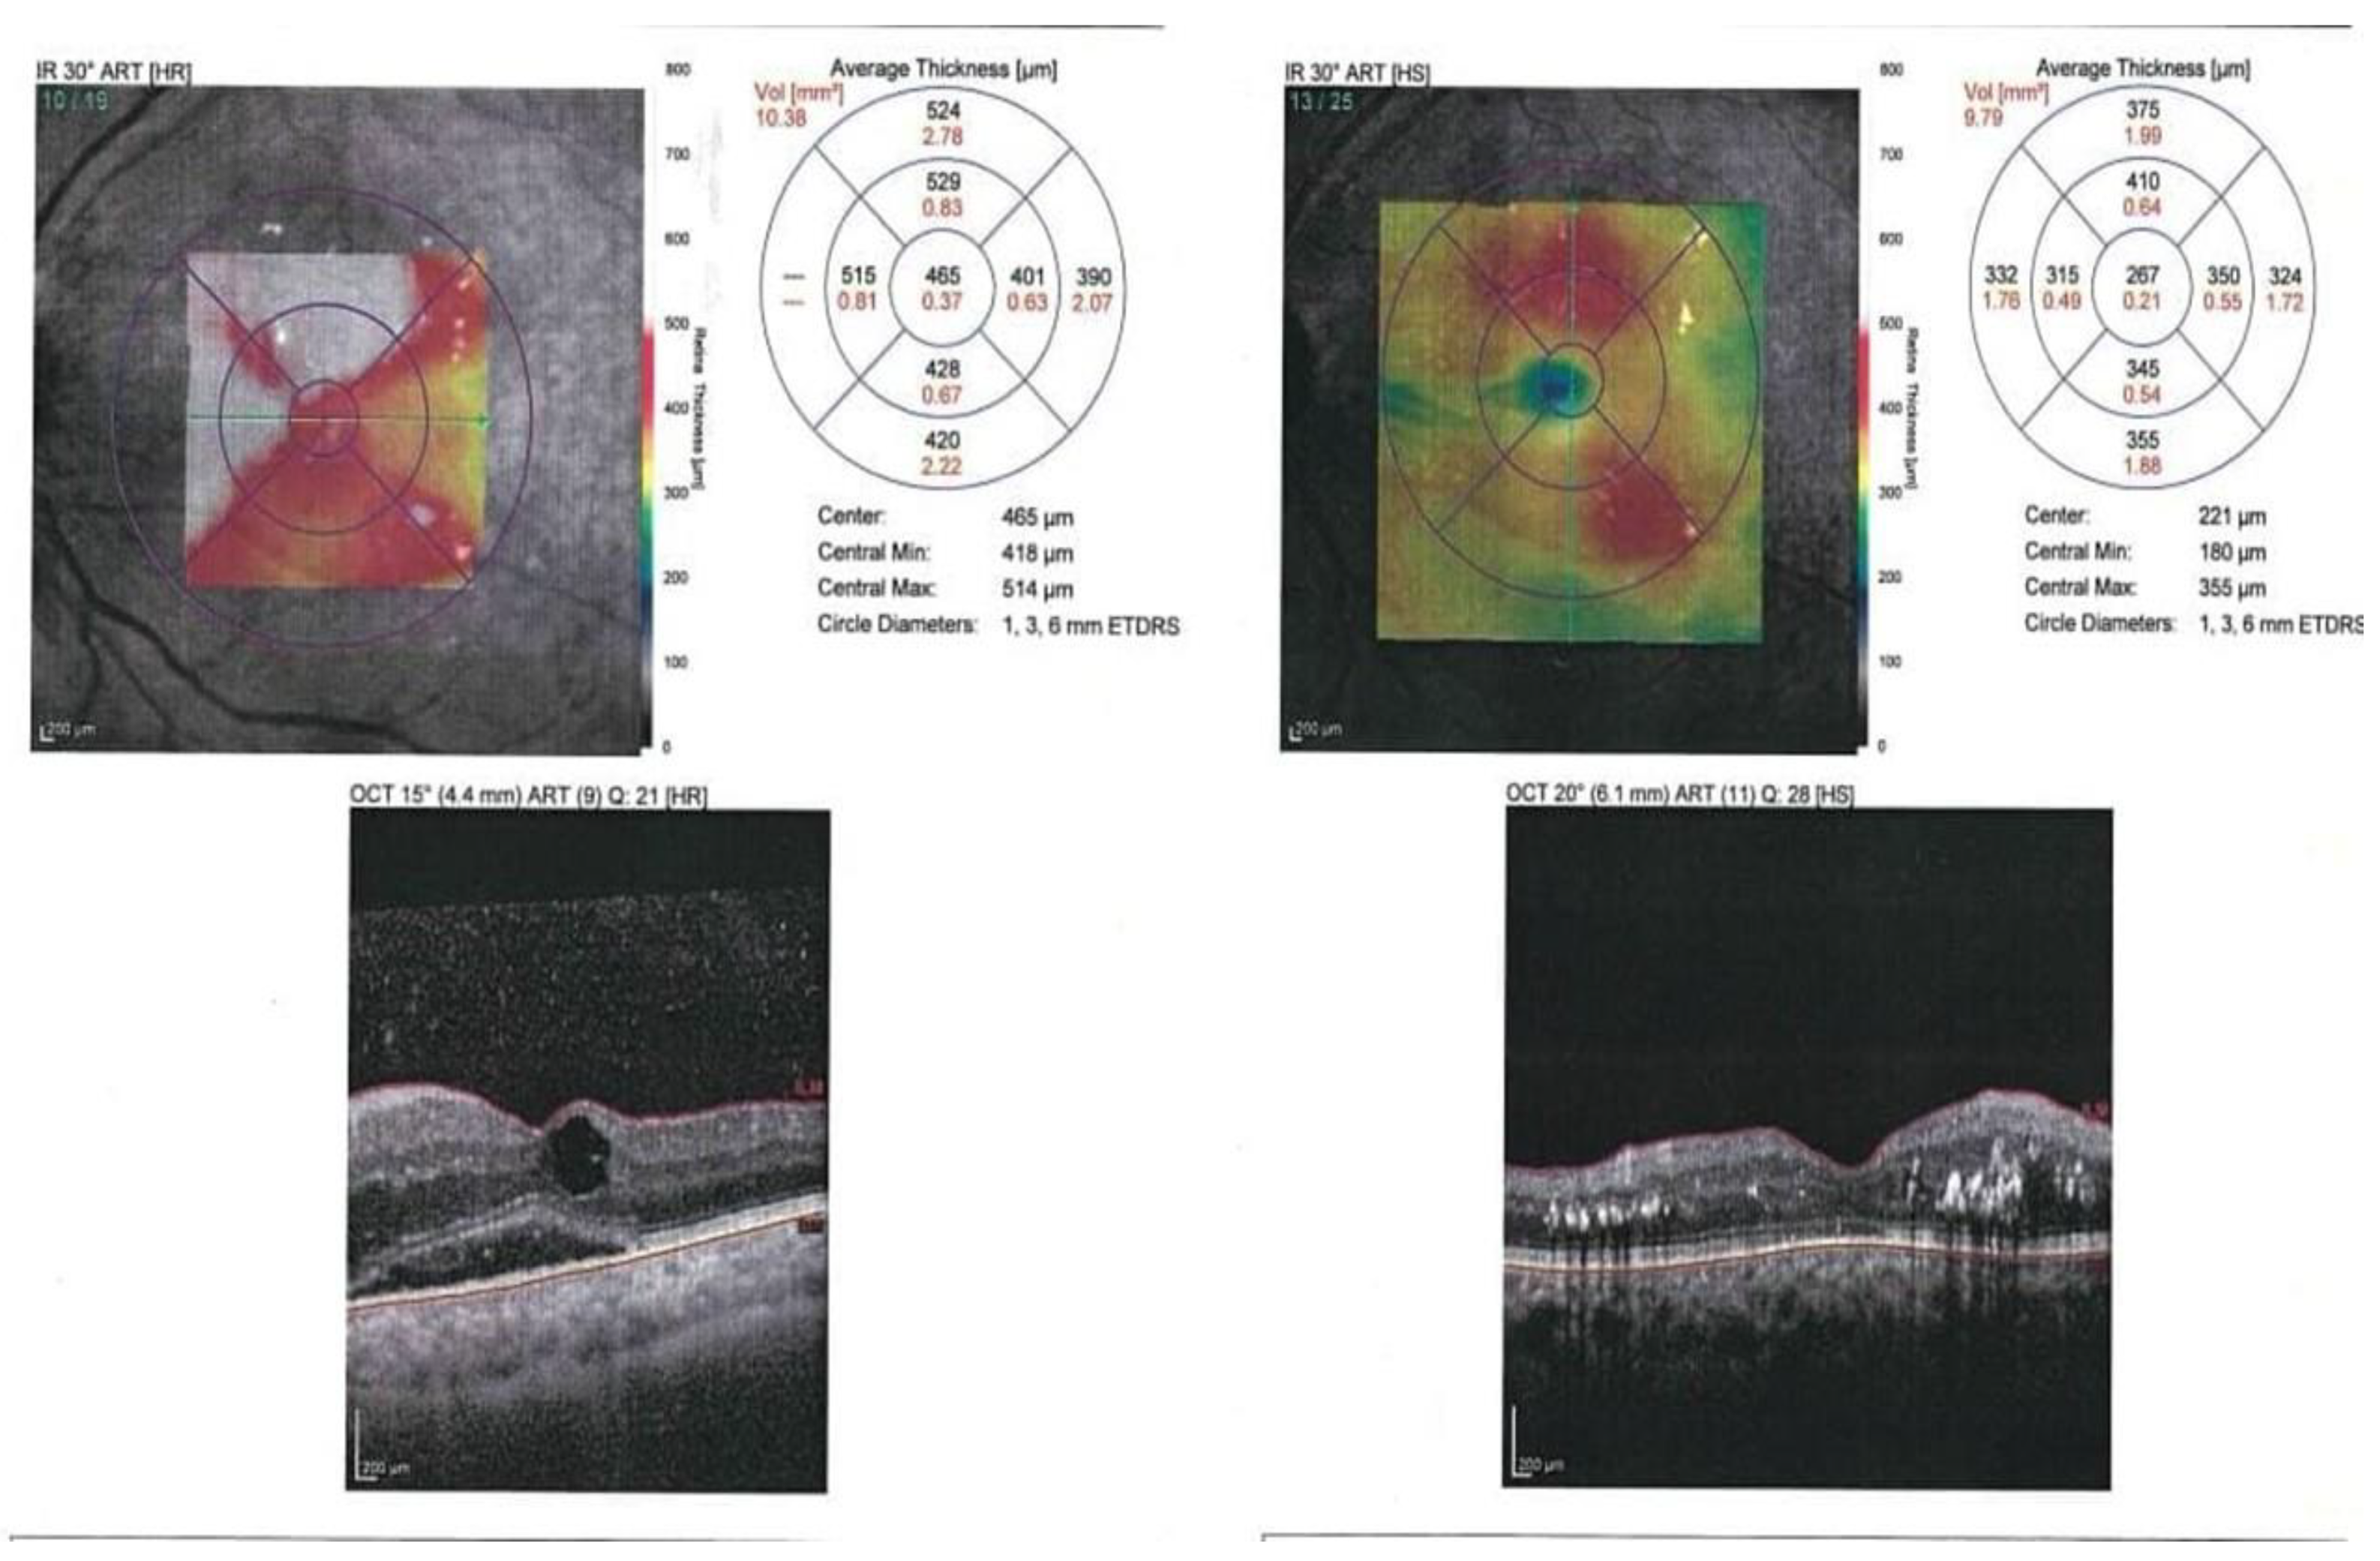

3.5. The BCVA, OCT Findings, and Macular Ischemia in the Patients with DME (Table 5)

| Variable | Non-Responders (n = 21 Eyes) | Responders (n = 43 Eyes) | t | p Value | ||

| BCVA (Log MAR) before IVR | 0.350 | 0.729 | ||||

| Mean± SD | 0.88 ± 0.11 | 0.87 ± 0.13 | ||||

| BCVA (Log MAR) after IVR | 7.838 | <0.001 * | ||||

| Mean± SD | 0.86 ± 0.25 | 0.55 ± 0.15 | ||||

| CMT (microns) | 0.637 | 0.529 | ||||

| before IVR | ||||||

| Mean± SD | 536.00 ± 84.52 | 516.44 ± 102.93 | ||||

| CMT (microns) | 4.702 | <0.001 * | ||||

| 1 month after IVR | ||||||

| Mean± SD | 514.92 ± 89.55 | 378.78 ± 77.35 | ||||